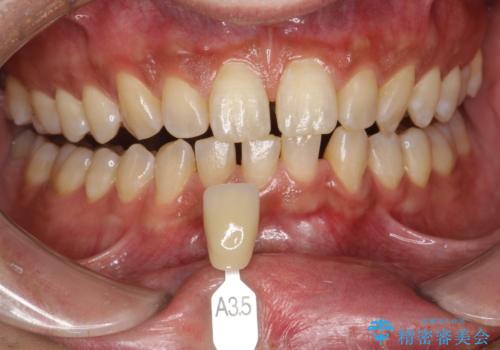

- ホワイトニングで、できる限り白くしたいとのことで来院されました。処置前クリーニング(¥3,300)・エクセレントホワイトニング(¥29,700)・トリートメント(¥550)を行いました。

ホワイトニング剤に含まれる過酸化水素・過酸化尿素には、歯を痛めることなく内部の色素を分解する力があります。ホワイトニング剤を塗布することで、より深いところの色素まで分解し、白くすることができます。